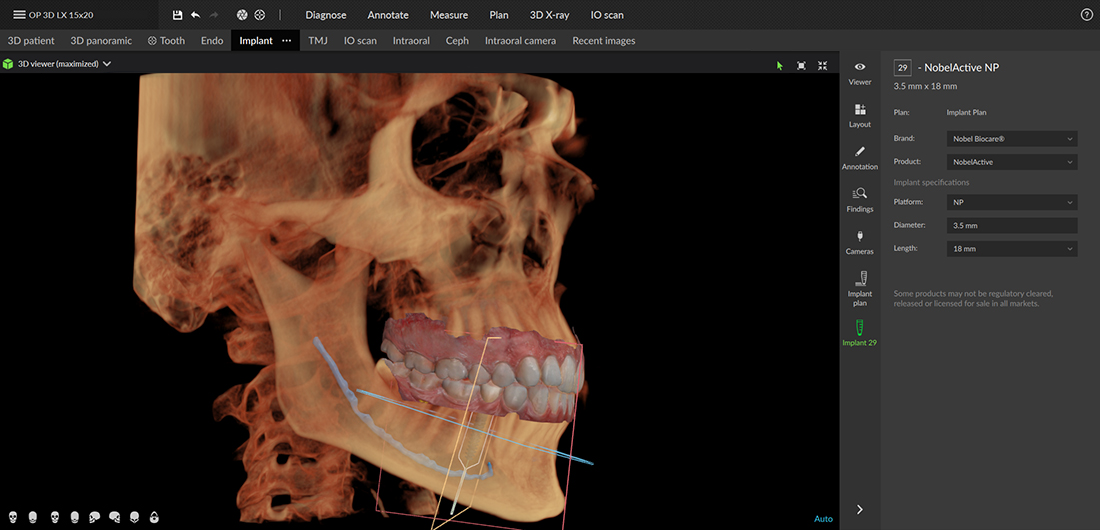

Implant placement

Whether it’s a single implant placement or the application of the All-on-4 technology, the DEXIS OP 3D LX enables multidimensional imaging for pre-surgical diagnosis and supports the most precise implant placement.

This next-generation system offers a flexible field of view (FOV), allowing for a variety of scans: from partial scans of 3-4 teeth (5 x 5 cm) to a full-face CBCT scan (15 x 20 cm), which currently represents the largest field of view available with the DEXIS OP 3D.

The 15×20 cm full-face scan is taken in a single exposure, not by stitching two images together, resulting in a lower radiation dose.